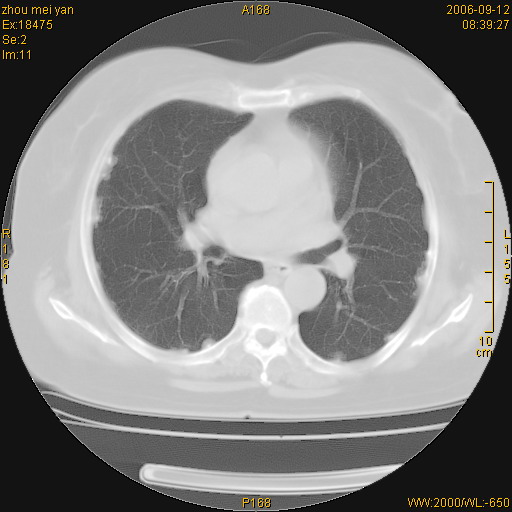

患者、女、55岁。因心率失常住院检查ct发现胸部多发结节。腹部b超肝、胆、胰、脾、肾、子宫附件未见异常。无结核病史,无粉尘接触史。请大家来会诊。谢谢!

胸膜间皮瘤可能性大。在气管隆突前可见一肿大淋巴结影。

病变位于胸膜,多发结节,边界清楚,内见小结节状钙化。其它未见异常。

考虑恶性胸膜间皮瘤可能性大,病灶位于胸膜,以宽基地与胸膜相连,呈结节样改变,部分病灶内可见点状钙化影。请各位老师多多指导!